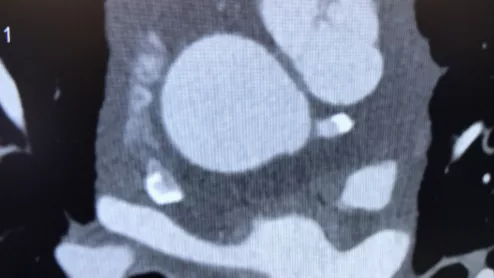

Iodine contrast being loaded into a contrast injector in preparation for a cardiac CT scan at Duly Health and Care in Lisle, Illinois. The contrast shortage is causing some healthcare organizations to postpone exams and procedures and ration contrast supplies. Photo by Dave Fornell

The American College of Radiology (ACR) announced this week its government relations staff has been engaging federal agencies in an effort to improve product availability and hasten resolution of the ongoing iodine contrast shortage.